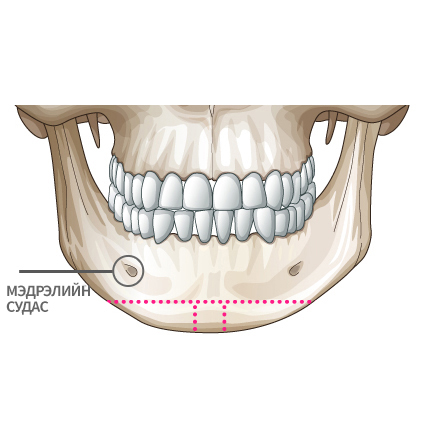

Мэдрэлийн судаснаас зайлсхийж, эрүүний төгсгөлд зүсэлт хийнэ.

Ясны гол хэсгээс тайралт хийж авна.

Харшил, сөрөг нөлөө бага. Мэдрэлийн судсыг холуур мэс засал хийх тул аюулгүй. |